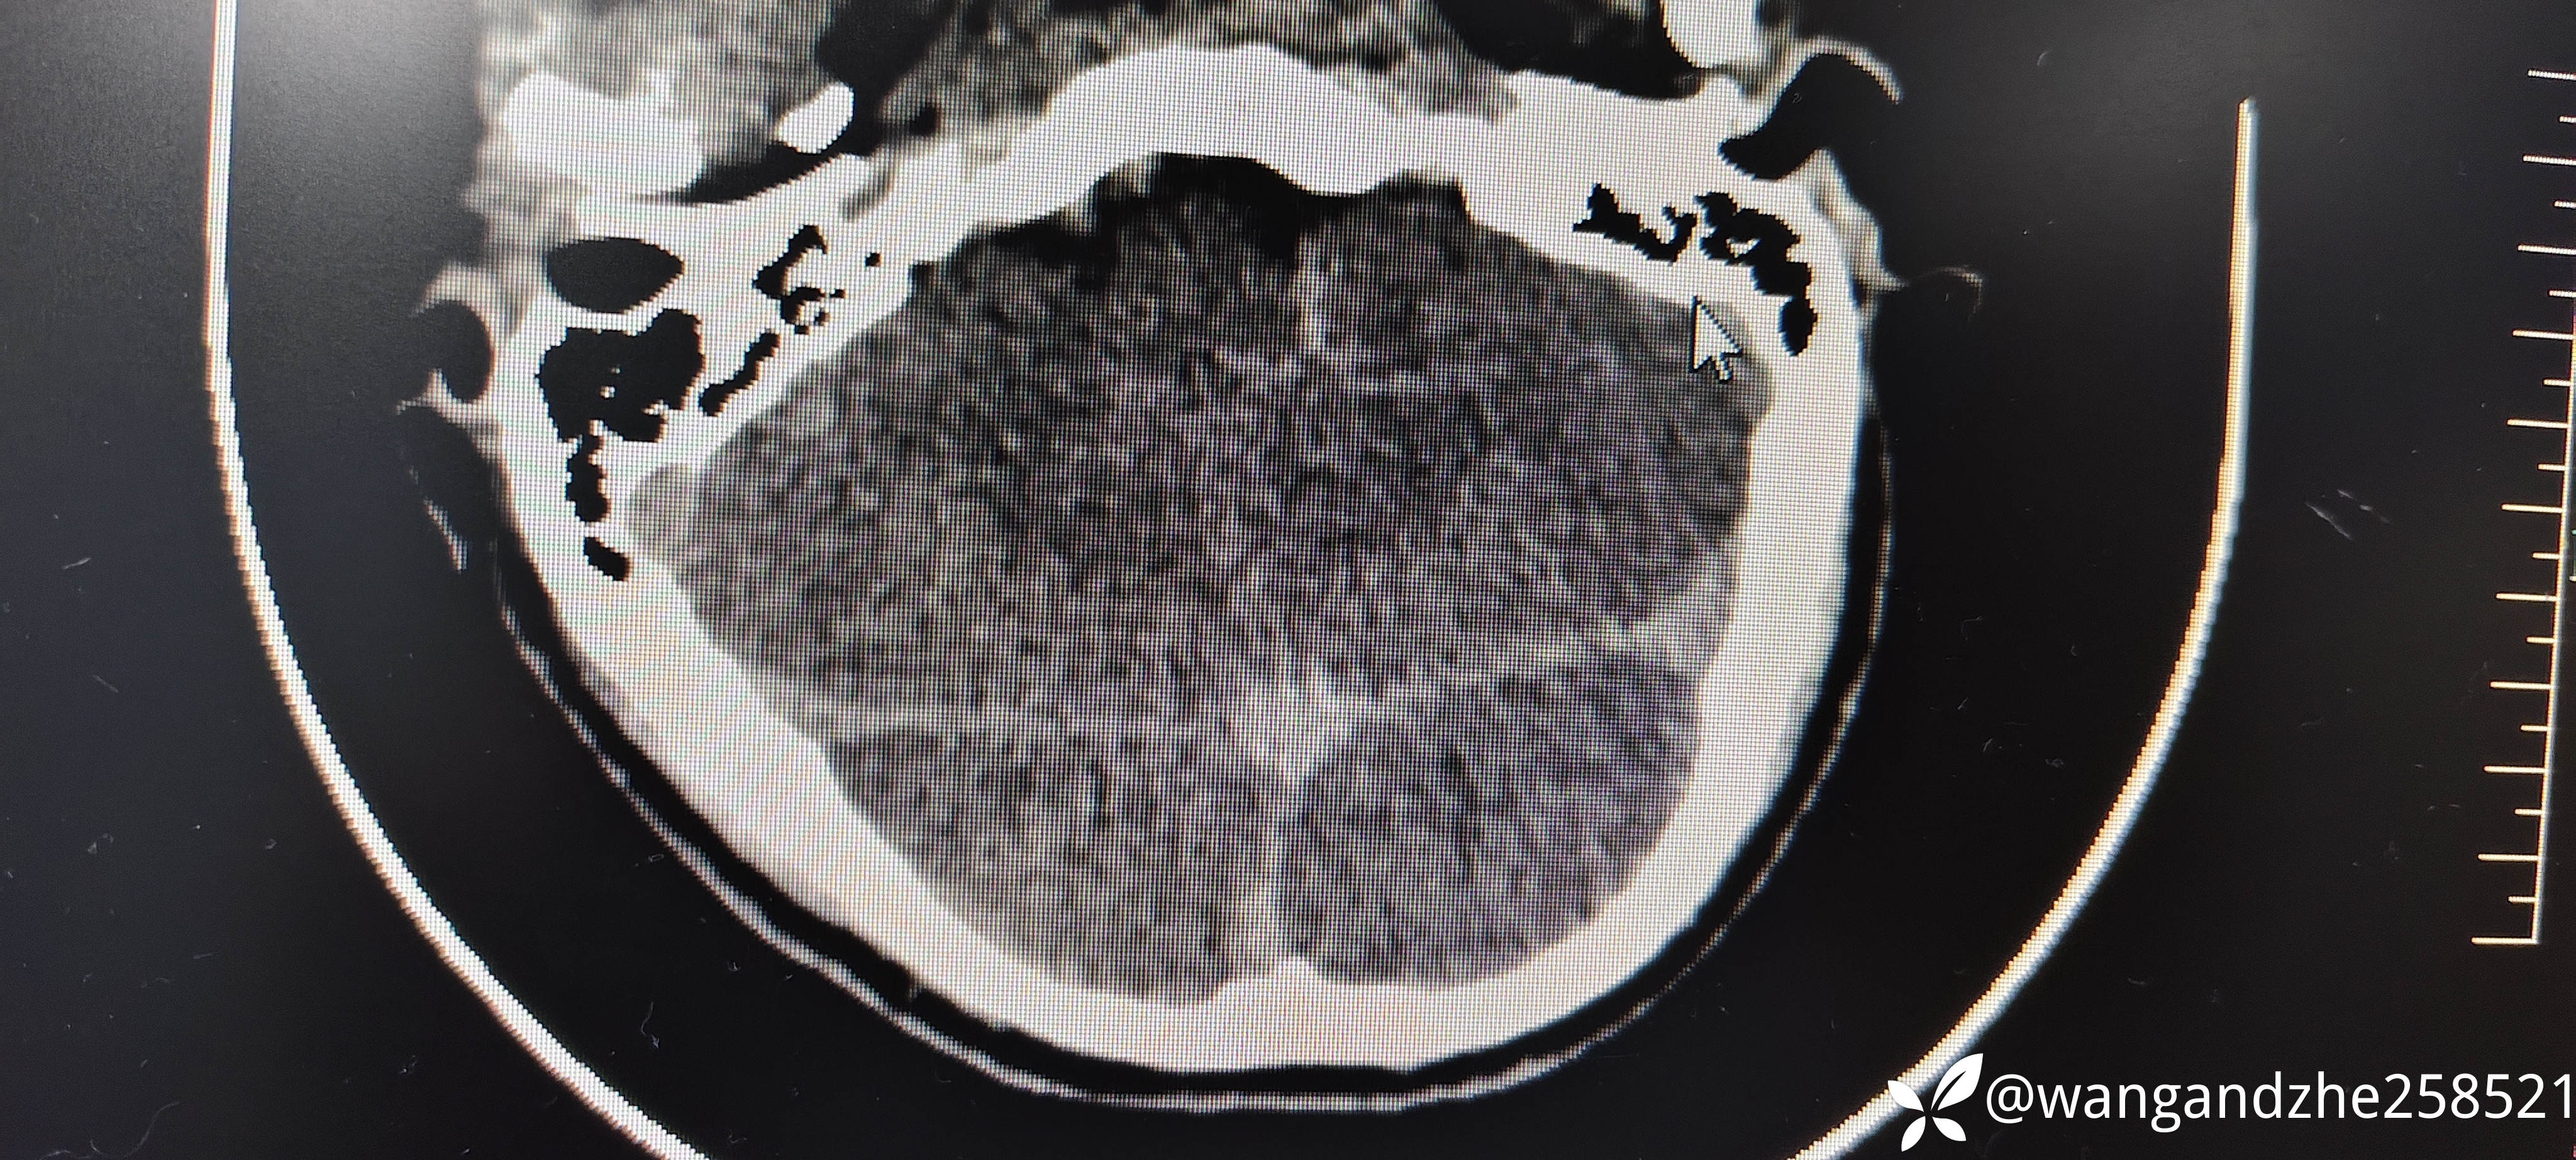

男性,21岁,酒后呕吐时出现呼吸心跳停止,陪人诉有窒息情况存在,现场给与胸外按压,后送外院就诊无生命体征,心电图示直线,给与心肺复苏等抢救后自主呼吸心跳恢复,意识无好转,为进一步救治送我院。既往体健。